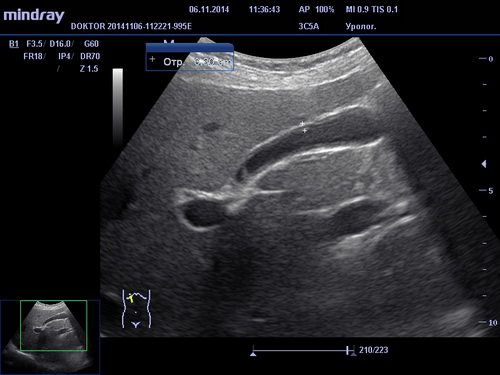

УЗИ брюшной полости

При помощи УЗИ брюшной полости возможна диагностика различных заболеваний и отклонений в состоянии печени, желчного пузыря, поджелудочной железы и селезенки, таких как холецистит, панкреатит, жировой гепатоз, хронический гепатит, цирроз печени, наличие опухолей и других образований. В зависимости от обследуемого органа и выявленной патологии пациенту назначается соответствующее лечение терапевтом, гепатологом или хирургом.